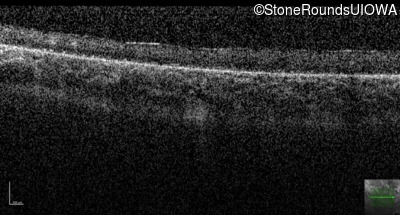

Optical Coherence Tomography - Left - Hand Motion sc

Exemplar